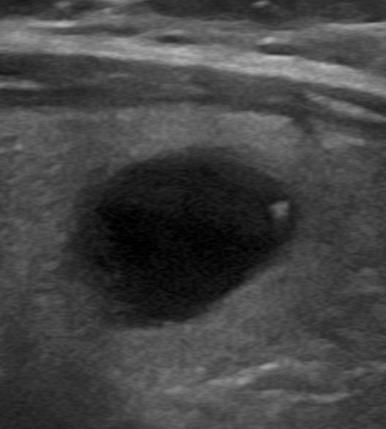

Ecografía tiroidea mostrando artefacto de cola de cometa en estructura quística

Visor ImagineUS®: Artefacto de cola de cometa en estructura quística tiroidea